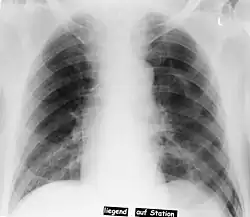

En radiología, el Signo del surco profundo en una radiografía de tórax supina es un indicador indirecto de neumotórax.[1][2]

En una radiografía supina, este signo se ve como un luminoso y profundo ángulo costofrénico ipsilateral,[3] dentro de las porciones no dependientes del espacio pleural en oposición al ápice (del pulmón) cuando el paciente está en posición vertical. El ángulo costofrénico es anormalmente profundo cuando el aire pleural se acumula lateralmente, produciendo el signo del surco profundo.[4]

Los pacientes con enfermedad pulmonar obstructiva crónica (EPOC) pueden mostrar ángulos costofrénicos profundos laterales debido a una hiperaireación de los pulmones y provocar un falso positivo para este signo.